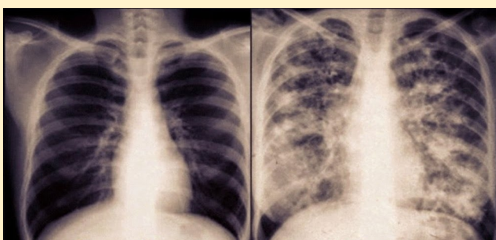

why is the lungs different

-patient has cystic fibrosis

-lots of mucus in lung

what is cystic fibrosis

-multisystem disease: lots of dif organs r affected

-not possible to treat

-genetic disorder

-autosomal recessive; both genes mutated in order for a person to have symptoms

-life shortening

-affects mostly lungs

cystic fibrosis symptoms

-thick sticky mucous blocks airways

-difficult to breath

-cough up mucus

-freq lung infection

-elevated sweat chloride levels

-dif ppl have dif deegree of symptom